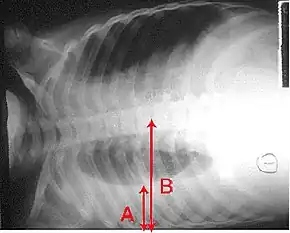

An X-ray showing a chest lying horizontal. The lower black area, which is the right lung, is smaller with a whiter area below it of a pulmonary effusion. There are red arrows marking the size of these.

A pleural effusion: as seen on chest X-ray. The A arrow indicates fluid layering in the right chest. The B arrow indicates the width of the right lung. The volume of the lung is reduced because of the collection of fluid around the lung.

In pneumonia, a collection of fluid may form in the space that surrounds the lung.[132] Occasionally, microorganisms will infect this fluid, causing an empyema.[132] To distinguish an empyema from the more common simple parapneumonic effusion, the fluid may be collected with a needle (thoracentesis), and examined.[132] If this shows evidence of empyema, complete drainage of the fluid is necessary, often requiring a drainage catheter.[132] In severe cases of empyema, surgery may be needed.[132] If the infected fluid is not drained, the infection may persist, because antibiotics do not penetrate well into the pleural cavity. If the fluid is sterile, it must be drained only if it is causing symptoms or remains unresolved.[132]